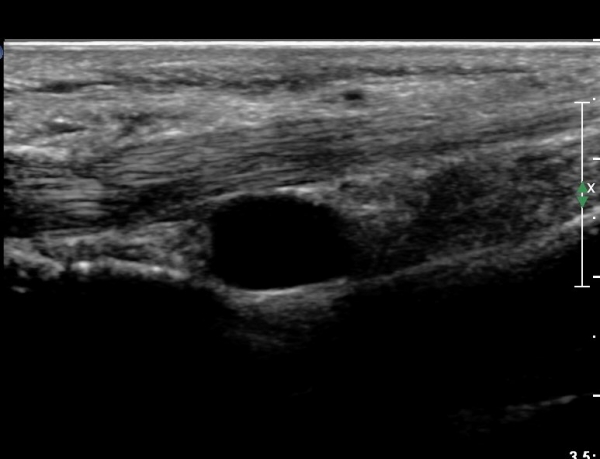

4 sono.jpg

¼Õ¹Ù´Ú ºÎÀ§¿¡¼­ ô°ñ½Å°æ ½ÉºÎ °¡Áö º´Áõ

(periphral neuropathy  of  deep palmar branch of ulnar nerve at palm level).